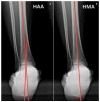

Adult acquired flatfoot deformity (AAFD) is a disorder caused by repetitive overloading, which leads to progressive posterior tibialis tendon (PTT) insufficiency. It mainly affects middle-aged women and occurs with foot pain, malalignment, and loss of function. After clinical examination, imaging plays a key role in the diagnosis and management of this pathology. Imaging allows confirmation of the diagnosis, monitoring of the disorder, outcome assessment and complication identification. Weight-bearing radiography of the foot and ankle are gold standard for the diagnosis of AAFD. Magnetic Resonance Imaging (MRI) is not routinely needed for the diagnosis; however, it can be used to evaluate the spring ligament and the degree of PTT damage which can help to guide surgical plans and management in patients with severe deformity. Ultrasonography (US) can be considered another helpful tool to evaluate the condition of the PTT and other soft-tissue structures. Computed Tomography (CT) provides enhanced, detailed visualization of the hindfoot, and it is useful both in the evaluation of bone abnormalities and in the accurate evaluation of measurements useful for diagnosis and post-surgical follow-up. Other state-of-the-art imaging examinations, like multiplanar weight-bearing imaging, are emerging as techniques for diagnosis and preoperative planning but are not yet standardized and their scope of application is not yet well defined. The aim of this review, performed through Pubmed and Web of Science databases, was to analyze the literature relating to the role of imaging in the diagnosis and treatment of AAFD.